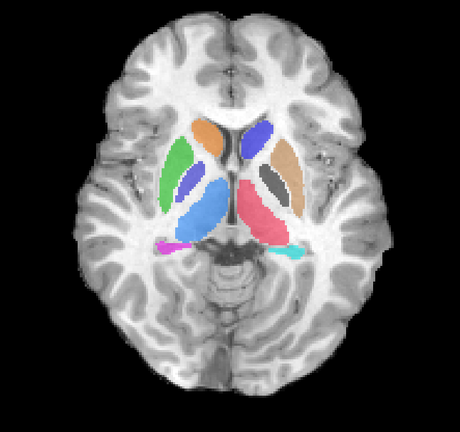

Left: Acquisitions of a single subject with observations at 1, 2, 4, 6, and 8 years old. Right: Sub-cortical structures are segmented for each time point.

Observations in time.gif 8yr with labels.png